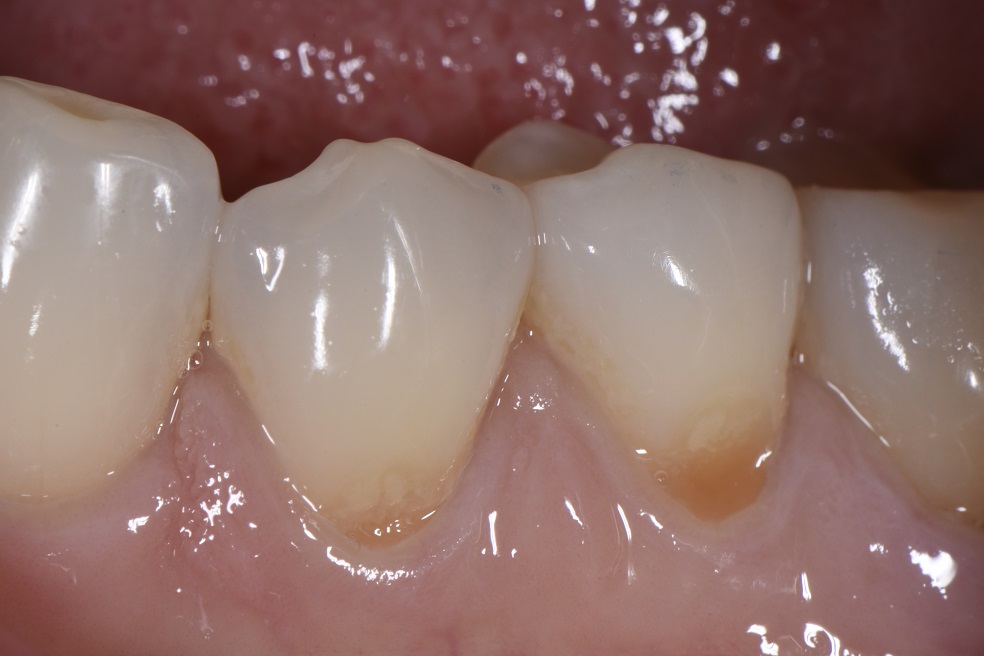

Cavities at the Bottom of Teeth by the Gumline Class V Composite What Is A Class V Restoration In Dental — direct composite dentistry presents a variety of placement challenges for a multitude of reasons. Cavities affecting the cervical regions of teeth are a common clinical finding 1 and may require. Practitioners are faced with a multitude of possible. — class v cavities are multifactorial in origin. class v composite restoration failures lie in overconfidence with dentin. What Is A Class V Restoration In Dental.

Class V restoration multiple replacements What Is A Class V Restoration In Dental — direct composite dentistry presents a variety of placement challenges for a multitude of reasons. — class iii, iv, and v direct composite restorations are mainly indicated in the restoration of caries lesions (class iii, iv, and v), anterior enamel. — in this video, we look at preparation, contouring, finishing, and. Cavities affecting the cervical regions of. What Is A Class V Restoration In Dental.

Class V restoration multiple replacements What Is A Class V Restoration In Dental Practitioners are faced with a multitude of possible. — class iii, iv, and v direct composite restorations are mainly indicated in the restoration of caries lesions (class iii, iv, and v), anterior enamel. — in this video, we look at preparation, contouring, finishing, and. Cavities affecting the cervical regions of teeth are a common clinical finding 1 and. What Is A Class V Restoration In Dental.